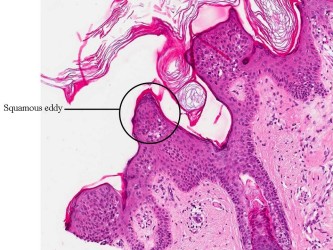

Histologie:Het histologisch beeld wordt gekenmerkt

door een scherp begrensde exofytisch of endofytisch groeiende tumor. Meestal

is er hyperkeratose en een papillomateus verbrede epidermis. De hyperkeratose

en de neiging van de retelijsten om te vergroeien, hebben de vorming van pseudo-hoorncysten

tot gevolg. De tumor is opgebouwd uit opvallend kleine spinale cellen. Basale

hyperpigmentatie is er in een derde van de gevallen. De epidermis toont geen

cytonucleaire atypie. Meestal zijn er geen afwijkingen in de dermis. In de dermis

van een geirriteerde verruca seborrhoica wordt echter een uitgebreid rondkernig

ontstekingsinfiltraat gezien met grensvlakactiviteit en soms met dyskeratotische

keratinocyten. Karakteristiek zijn de zogenaamde “squamous eddies”, nesten van

keratinocyten. Het Borst-Jadassohn type, ookwel het clonale type, is te herkennen

aan intra-epidermale nesten van spinale cellen.